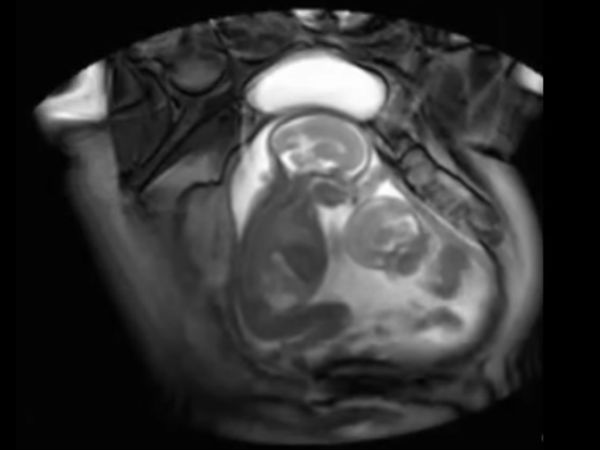

சிசு கர்ப்பம்!

சில சமயங்களில் கருவில் இரட்டையர்கள் தரிக்கும் போது, ஒரு சிசுவின் உடலில் ட்வின் சிசு சிக்கிக் கொள்ள வாய்ப்புகள் உண்டு. சிசு உருவாகும் பொது, வளரும் போது ஏற்படும் கோளாறாக காணப்படுகிறது. சில சமயங்களில் கூடுதல் உடல் உறுப்புகளுடன் பிறப்பது. ஓட்டிப் பிறப்பது, வளராத கூடுதல் உறுப்புகளுடன் பிறப்பது எல்லாம் இப்படிப்பட்ட கோளாறால் தான் நிகழ்கின்றன.